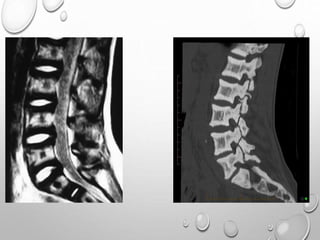

VERTEBRAE

LUMBOTHORACIC KYPHOSIS

LUMBER HYPER LORDOSIS

LENGTH GENERALLY NORMAL

PLATYSPONDYLY , DISC HEIGHT EQ TO VERTEBRAL BODY

POSTERIOR SCALLOPING

PEDICLES ARE SORT , THICK , INTERPEDICULAR DISTANCE DECREASED

ANGULAR KYPHOSIS AT THORACOLUMBER JUNCTION RESULTING FROM

ANTERIOR BEAKING OR BULLET NOSE VERTEBRAE

SPINAL CANAL STENOSIS ---- PATHOLOGIC HALLMARK

SPINE : SEVERE SCOLIOSIS , KYPHOSCOLIOSIS

SPINAL CANAL WIDENED >50% OF CASES

POSTERIOR VERTEBRAL SCALLOPING

PEDICLE , LAMINA ARE SLENDER

INTERPEDICULAR DISTANCE INCREASED

THESE ARE DUE TO DURAL ECTASIA